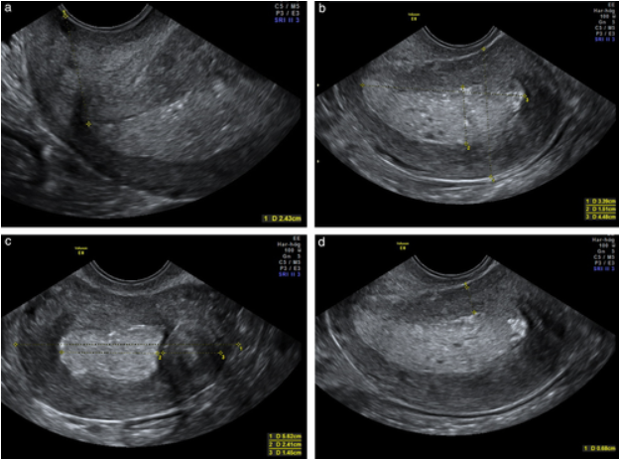

초음파, 그중에서도 산부인과 초음파는 극히 어렵다. 수많은 의사들 중에서 자궁 초음파는 하는 의사는 산부인과와 영상의학과 의사뿐이다. 왜냐하면 초음파 자체는 방사선이 없어 사람은 물론이고 태아에게 무해하나, 초음파 검사 결과가 이상한 것인지 감별하지 못하면 환자에게 큰 해를 끼치기 때문이다. 그리고 무려 2010년 3월부터 2012년 6월까지 27개월에 걸쳐 68회(12일에 한 번 꼴)나 한의사가 초음파를 했으나, 자궁내막암 2기를 전혀 진단하지 못했다. (자궁내막암이라서 그나마 다행이었다. 자궁 외 임신을 놓쳤으면, 환자가 즉시 사망할 수 있다.) 이로써 환자에게 도움이 되기는커녕, 큰 해를 끼쳤다.

<초음파의 특징: CT와 달리 경계 등이 명확하지 않아, 시술자에 따라 천차만별이고 또한 잘 모르는 사람을 상대로 속이기 매우 쉽다> 출처1)